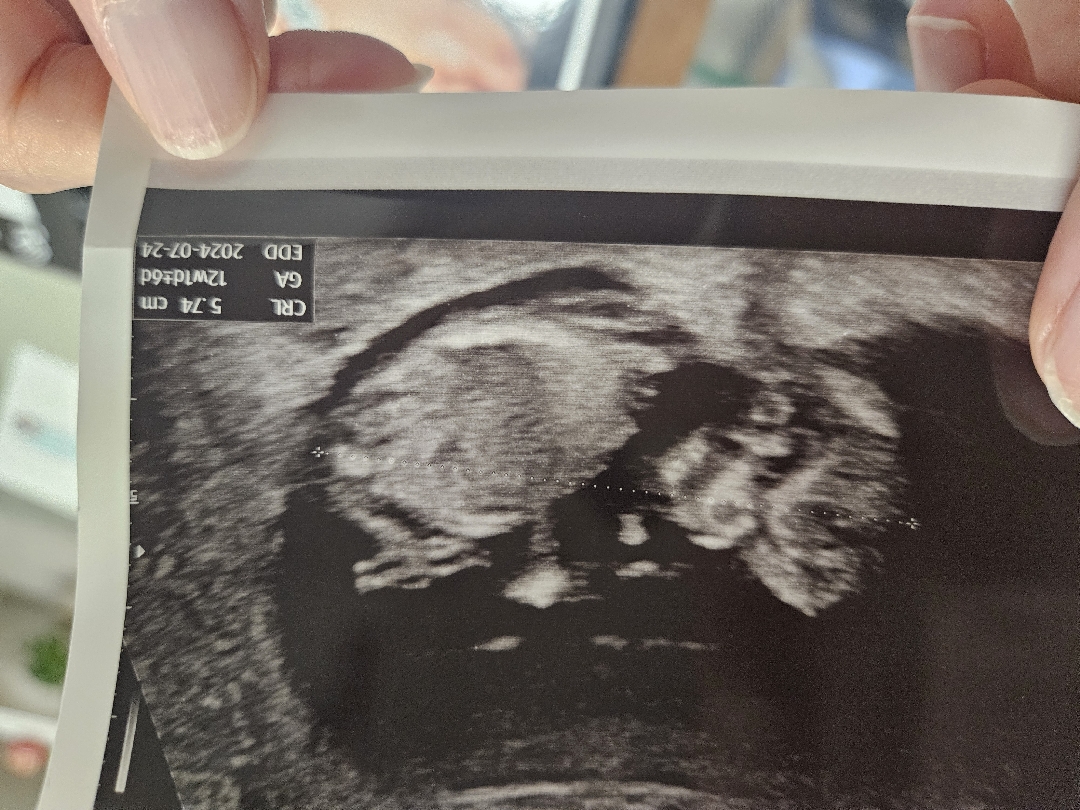

12주차 성별이 어떨까요ㅠㅠ

입체초음파 보면 고튜같은게 보이긴하는데.. 울퉁불퉁한게 정확한것도 아니라서.. 어때보이세요?